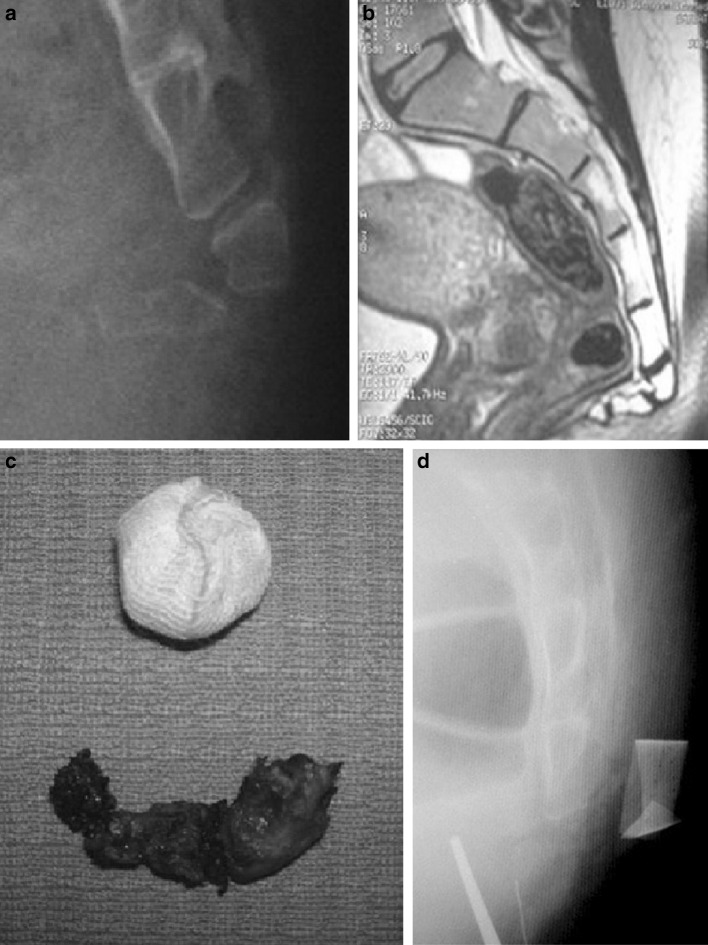

Dietary restrictions were followed 3–5 days before surgery and patients undergoing surgery had a pre-operative enema. While giving anaesthesia, 2 g Cephazoline were administered. Patients were prone-positioned with flexed hip and buttocks slightly spread open by means of plaster aid, with the aim of stretching skin on the intergluteal line. Adhesive sterile drapes were placed on site after skin disinfection. We performed coccygectomy following Key’s technique [10], as thoroughly described by Bilgic et al. [14] in their Group 1 patients. We never used sub-periosteal technique [14]. Unstable, mobile fragment was excised en-bloc via a trans-discal approach, including its periosteum. We performed a total of 21 total coccygectomies with three fragments removal (Fig. 1a–d), while seven partial coccygectomies were performed resecting two bony fragments (Fig. 2a–d). Discectomy was always performed in a radical way, and when protrusion of the sacrum or of the first coccygeal vertebra occurred, a rongeur was used for bone contouring. Resection was confirmed by radiograms taken at the end of the surgery. Anatomical sample was cleaned and pictures were taken. An accurate hemostasis and several washings with saline and Gentamycine were carried out, and wound closure was performed in a three-layer fashion [3]. If torn, pre-sacral fascia was carefully closed with resorbable sutures. No resorbable skin sutures and/or drainage were used. Surgery duration was always less than 80 min (mean 65; range 50–80). Therefore, no supplemental antibiotics were administered.

Fig. 1.

a Preoperative X-ray in standing position. Coccygeal fracture-dislocation Maigne type I (Postacchini type III); b preoperative MRI shows the severe anterior luxation and complete instability of the coccix; c specimen after total coccygectomy (3 fragments); d intraoperative X-ray confirms total resection